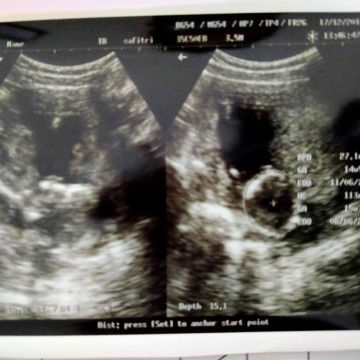

Sedikit berbagi cerita ya bund memang selama hamil saya harus tetap bekerja, bulak balik ke sekolah untuk ngajar dan bawa motor sendiri ? Tepat hari senin lalu pada saat brangkat kerja harus mengalami kecelakaan motor, badan pada memar, tangan kanan terkilir. Saat kecelakaan yang saya pikirkan bagaimana keadaan bayi saya ? ? apakah baik baik saja ? ? dalam hati saya masih merasa bersyukur karena saya masih diberi keselamatan, disisi lain pikiran udah kemana mana kepikiran yang di dalem perut. Akhir nya setelah kecelakaan tangan kanan saya langsung di urut dan memang bener, tangan kanan saya terkilir dan sampai sakit saat digerakkan. sore nya saya langsung cek ke bidan. Dalam hati saya berharap semua baik baik saja ? Alhamdulillah nya setelah kecelakaan saya gak ngalamin ngeflek bund , hanya perut saja yang ngerasa kram dan sekujur badan sakit akibat memar. pas di cek bidan, bidan gabisa matiin anak saya baik baik saja atau enggak ? harus di USG. sayangnya, hari itu di bidan tersebut sedang tidak ada USG, saya pulang dan cuma dkasih vitamin plus penguat kandungan ? selama dikasih obat itu kalo saya terjadi flek harus segera ke UGD RS terdekat. nyari USG ke klinik atau bidan terdekat sama belum ada jadwal USG, yang paling dekat seminggu baru ada jadwal USG di salah satu klinik. Kenapa saya gak USG ke RS ? rumah saya di pelosok bund, jauh sekali untuk ke RS yang terdekat. Oke akhirnya saya harus sabar dan nunggu seminggu. pas jadwal USG tiba saya takut, takut terjadi apa apa dengan kandungan saya. dannnnn alhasillll Alhamdulillah ya Allah Janin di dalam kandungan saya baik baik saja, Ya Allah rasa nya legaaa ternyata anak saya kuat maafin bunda ya de besok bunda janji harus lebih hati hati lagi semoga kedeoan nya kamu selalu sehat ya nak ? amiin pesan untuk bunda bunda lain selama kehamilan lebih baik hindari bawa motor sendiri dlu deh bund, takut kejadian nya kayak saya lebih baik dibonceng, atau naik angkutan umum . Semenjak kejadian itu saya gapernah bawa motor sendiri lagi pasti minta dianter sama orang terdekat. Semoga bunda bunda disini selalu diberi kesehatan ya Bunda dan janin yang sedang dikandung nya ?